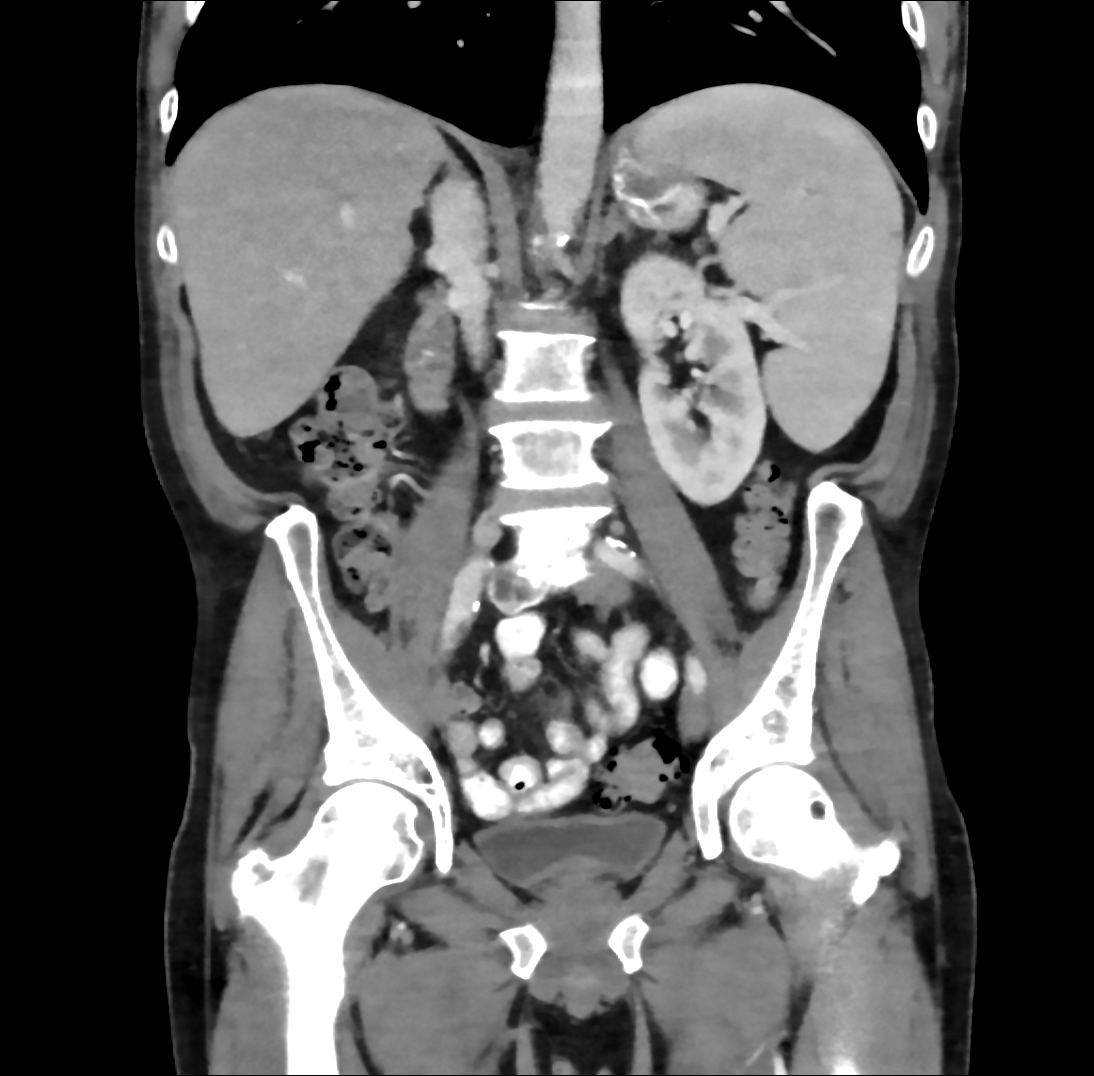

Case Presentation: 61-year-old man with coronary artery disease, tobacco use, and partial R toe amputation after trauma presented to an outside hospital with 3 months of fevers, night sweats, and 30 kg weight loss. He was found to have pancytopenia, splenomegaly, and retroperitoneal lymphadenopathy raising concern for malignancy. These findings prompted a bone marrow biopsy which showed trilineage hyperplasia without evidence of hematological or metastatic neoplasm. Extensive coronary calcifications were incidentally noted on imaging. He was discharged with plan for Hematology and Cardiology follow-up. He presented to our hospital with persistent symptoms. On exam, he was febrile to 39.2C, tachycardic, and had a 3/6 holosystolic murmur at the apex. Labs showed pancytopenia with WBC 4.5, hemoglobin 8, and platelets 47K. Blood cultures were obtained and vancomycin, cefepime, and azithromycin were administered. In less than 24 hours, blood cultures returned positive for streptococcus parasanguinis and antibiotics were narrowed to ceftriaxone. Transthoracic and transesophageal echocardiograms demonstrated a large (1.4 x 0.6 cm) pulmonic valve vegetation with severe pulmonic valve regurgitation and ruptured posterior mitral valve leaflet chordae with severe mitral valve regurgitation. The size of the vegetations and degree of valvular dysfunction prompted urgent surgical consultation and he subsequently underwent pulmonic and mitral valve replacement with concurrent coronary artery bypass grafting for high grade right coronary artery stenosis. Intraoperative exam demonstrated large pulmonic valve vegetations and bi-leaflet mitral valve vegetations. Withing 72 hours of antibiotic initiation, he reported clinical improvement with resolution of fevers and night sweats and improvement in his appetite and energy level and subsequently completed a 6-week course of ceftriaxone. Interestingly, during his admission to our hospital, his prior bone marrow biopsy was reviewed and found to be suggestive of low-grade myelodysplastic syndrome (MDS). On most recent laboratory testing, obtained at completion of antibiotics, he remains mildly pancytopenic.